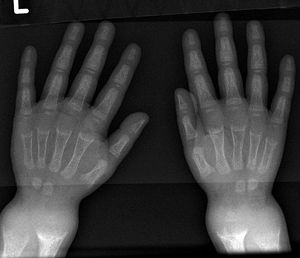

Name the deformity and the disease in which it occurs?

Rickets/ hypothyroidism causing delayed milestones

Rickets /hypothyroidism causing delayed milestones